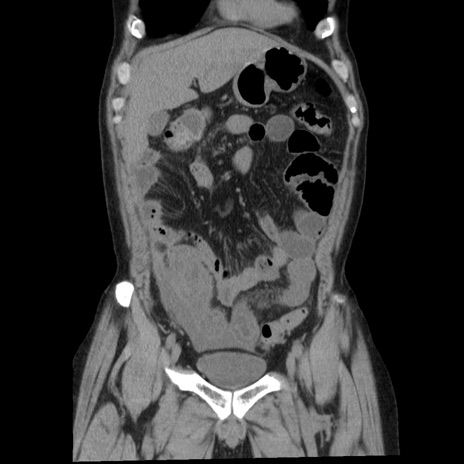

横断像

【症例】40歳代男性

【現病歴】2日前から胃痛あり。徐々に周期的な激痛に変化した。本日になっても激痛があるため受診。

【身体所見】意識清明、BT 38-39℃台あり、腹部:膨満、やや硬、右下腹部に圧痛あり。

【データ】WBC 8500、CRP 23.26